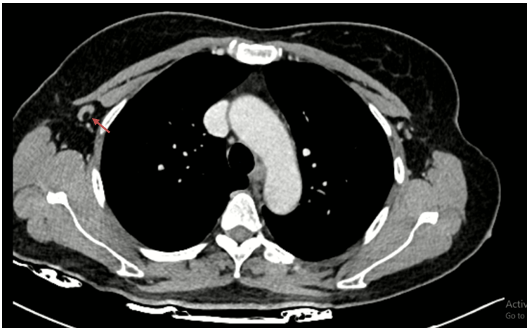

Chụp cắt lớp vi tính lồng ngực có tiêm thuốc: Hình ảnh nốt đặc nhỏ thùy dưới phổi phải. Dải xẹp thùy giữa phổi phải. Nốt ngấm thuốc 1/4 dưới ngoài vú phải đường kính 20mm, bờ ranh giới không rõ, ngấm thuốc sau tiêm.

Hình 3:

Hình ảnh nốt ngấm thuốc 1/4 dưới ngoài vú phải đường kính 20mm, bờ ranh giới không rõ, ngấm thuốc sau tiêm (mũi tên đỏ).

Hình 4:

Hình ảnh hạch nách phải còn cấu trúc rốn hạch, kích thước ~ 18x7mm (mũi tên đỏ).